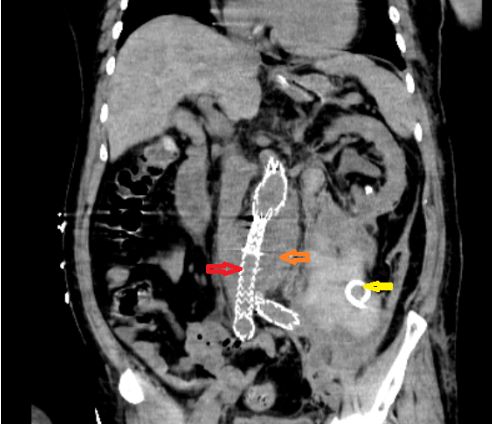

CT可以看到动脉瘤内支架(红色箭头)、动脉瘤样扩展(橘色箭头)、腹膜后血肿及引流管(黄色箭头)。